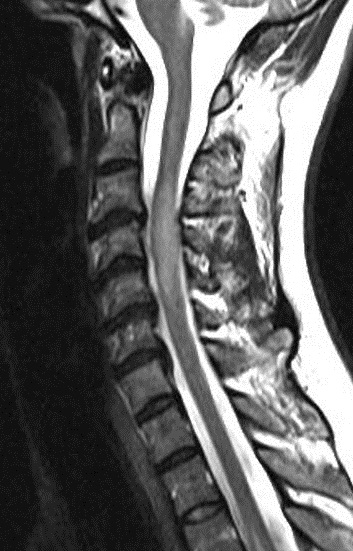

A MRI scan of brain and spine showed increased T2 signal and expansion of the cord in some areas of the spinal cord at the levels of C2–C5, and C7 to T12. The patient was given methylprednisolone 1 gram intravenous for a period of 5 days and oral steroids for 4 weeks. Thyroid function tests were reported to be normal (Table 3 [Tab. 3]). The patient showed marginal improvement in vision and reduction of sensory abnormalities by about 50% over a period of 6 weeks. In April 2015, the patient was admitted with cough associated with mucopurulent expectoration, shortness of breath, paraesthesias and diminished vision. The patient showed minimal improvement in sensory symptoms or vision. In May 2015, the patient was admitted with progression of bilateral lower limb weakness, bilateral upper limb weakness (distal > proximal) and a band-like sensation around the chest, syncope, vomiting and hiccups. Clinical examination revealed normal higher mental functions with diminished vision to finger counting in the right eye. Other cranial nerves were normal.

Immunological tests for ANA titer were 1:320, tests for anti-ENA, anti-dsDNA, anti-cardiolipin, anti-β2GPI, lupus cells, antibodies to GAD65, IA-2, insulin and cryoglobulins were negative. MRI brain and whole spine revealed 1) hyperintensity in cervical cord C5 to C7 level (Figure 1 [Fig. 1], Figure 2 [Fig. 2], Figure 3 [Fig. 3]); 2) hyperintensity in the thoracic cord till T12 level (Figure 4 [Fig. 4], Figure 5 [Fig. 5], Figure 6 [Fig. 6]); 3) hyperintensity in the right optic nerve head (Figure 7 [Fig. 7]). The clinical features and investigations (NMO IgG was positive) fit into the criteria of neuromyelitis optica. The thyroid profile was suggestive of hypothyroidism (Table 3 [Tab. 3]). Laboratory studies confirmed the presence of antithyroid antibodies (Table 4 [Tab. 4]). Fine needle aspiration of the thyroid showed lymphocytic infiltration of the thyroid gland (Figure 8 [Fig. 8], Figure 9 [Fig. 9]). The patient was treated with prednisolone 1 g/day for 5 days and azathioprine (2.5–3 mg/kg/daily). The patient showed improvement in motor symptoms and sensory symptoms approximately by 60% after a period of 2 months of treatment. Patient was started on thyroxine 50 μg and later dosage was increased to 100 μg.